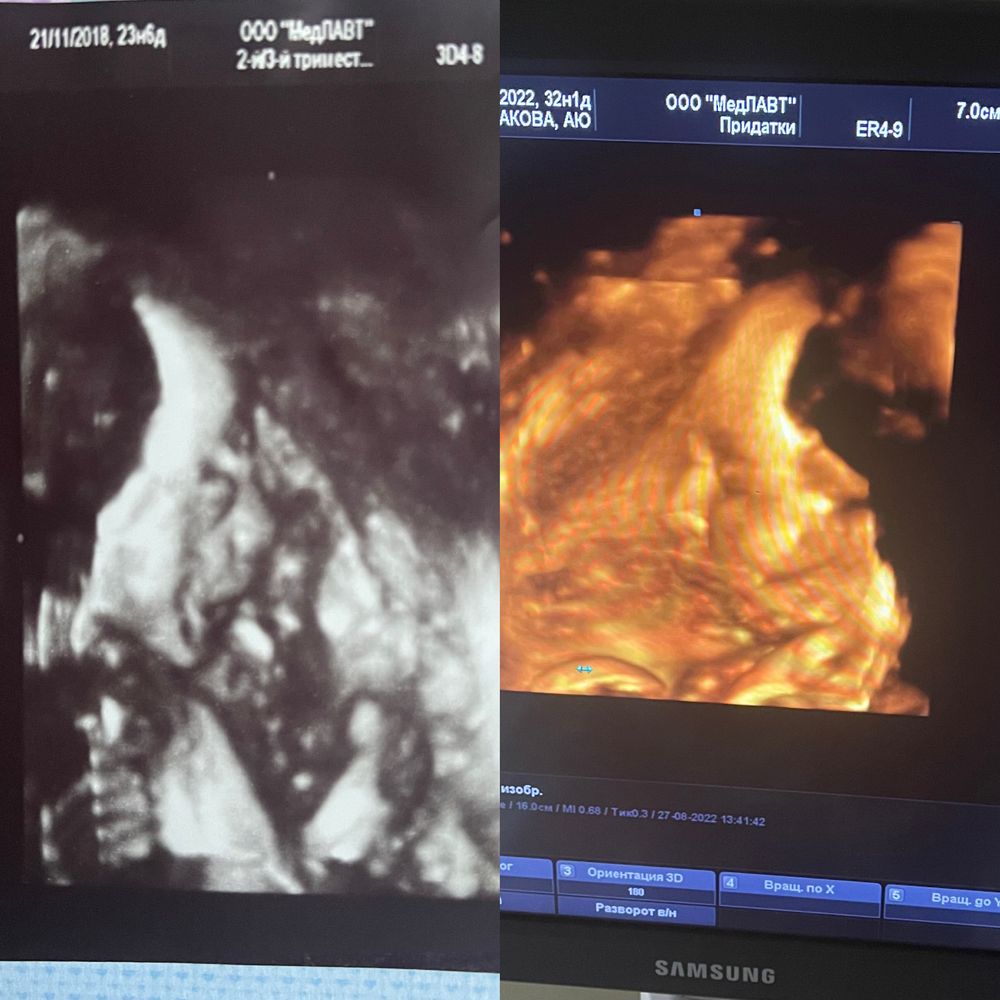

Анастасия , слева первый ребёнок в 23 недели, худощавый, справа второй в 32 там прям жирочка уже накопила

так что если у вас впереди то особо не Надейтесь, а если по задней то конечно до 33 недель где то можно сделать хорошее фото ☺️ чем больше срок тем симпатичнее фото